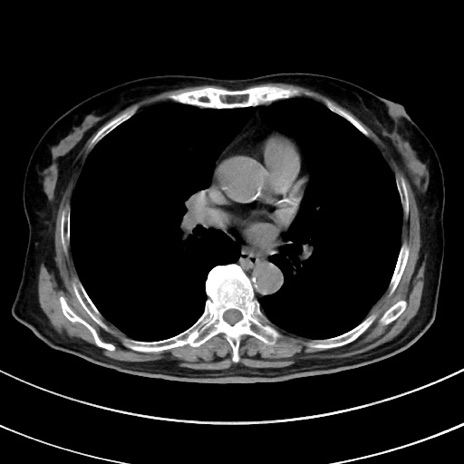

症例33(横断像)

【症例】70歳代 女性

【主訴】心窩部痛

【現病歴】延髄病変の精査・加療にて神経内科入院中。本日より心窩部痛あり。

【既往歴】虫垂炎

【身体所見】右下腹部を中心に圧痛と反跳痛あり。

【データ】WBC 10900、CRP 0.02